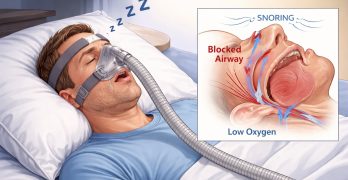

La Asociación Americana de Ortodoncistas (AAO) ha publicado una importante actualización de su "white paper" sobre los … [Leer más...] acerca de ¡Lectura Indispensable! La AAO actualiza su Guía sobre trastornos respiratorios del sueño y ortodoncia

Main Content

¡Lectura Indispensable! La AAO actualiza su Guía sobre trastornos respiratorios del sueño y ortodoncia